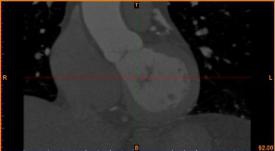

病例描述:

病人患冠心病,堵塞處較多,決定采用搭橋治療。

醫(yī)生需求:

需要準確定位病灶位置,加快手術時間。

建模過程:

首先通過病人的心臟冠脈造影CT數(shù)據(jù),獲取病人的心臟冠脈三維模型。

病人的冠脈造影CT數(shù)據(jù)                                              提取出的冠脈三維數(shù)據(jù)